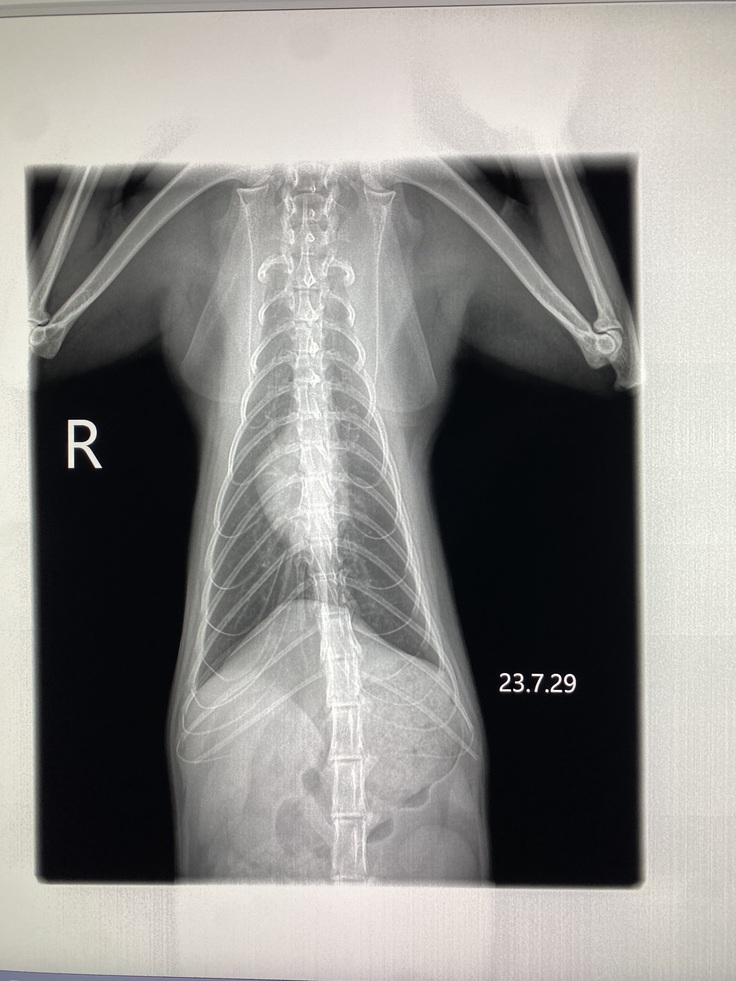

これから、レントゲンやエコー、血液検査です。状態がよければ抗がん剤治療2クールに入ります。獣医師が、私の費用負担を抑えるために毎週レントゲンはやらずに、エコーで頑張って見てくださっていたので、一か月ぶりです。転移はないのか、腫瘍はどうなっているのか、不安です。

レントゲン、血液検査、非常に良好にて、抗がん剤治療2クールめ、スタートです。今日は、ピンクリスチン。昼に治療するので、16時にお迎えします。体重は、先週と変わらず、3.56キロ。食べたのに何故だろう。

胸水も腫瘍もなく、きれいだそうです。